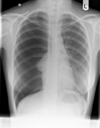

Normal